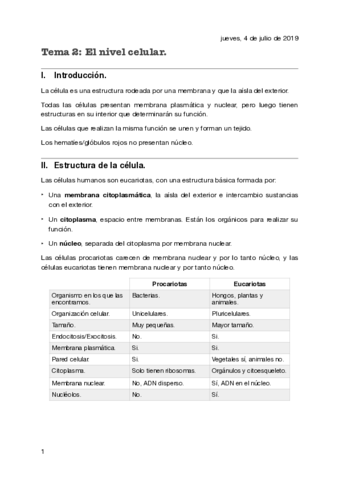

He publicado nuevos apuntes de Fisiopatología general: tema-2-la-celula.pdf